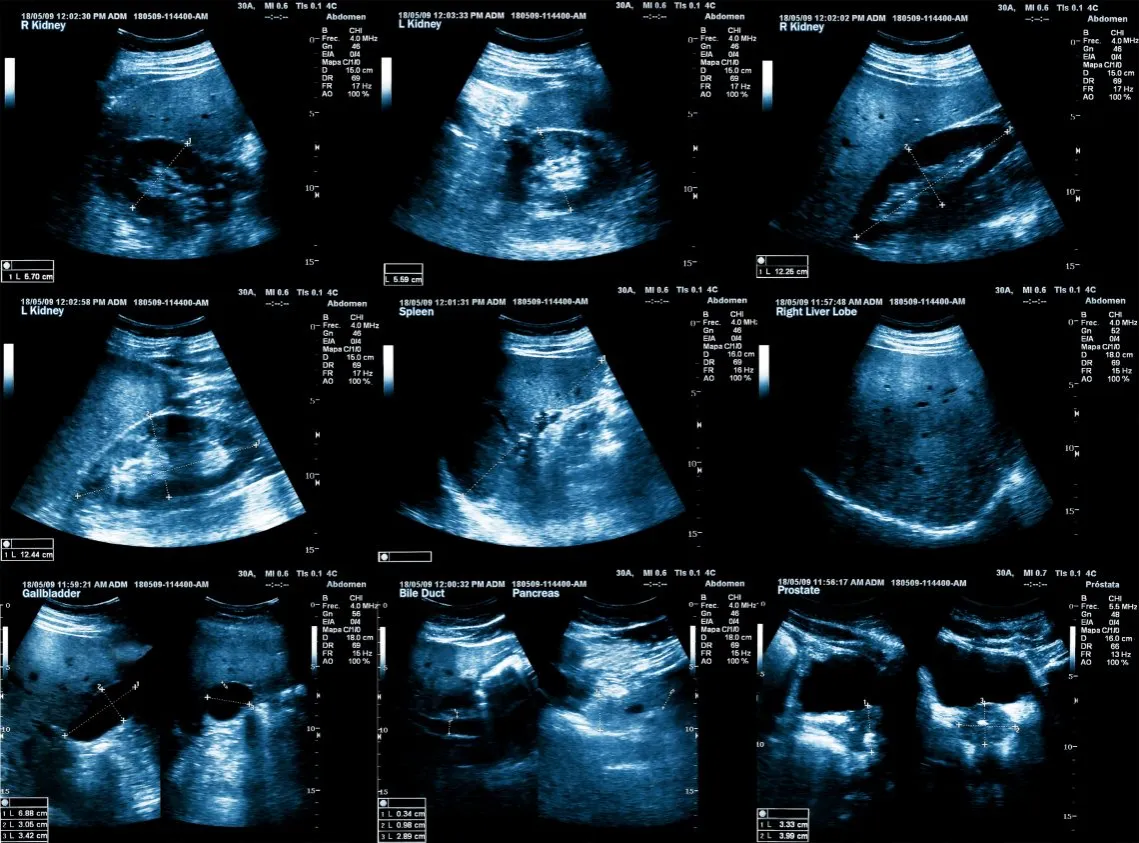

- USG jamy brzusznej: Pozwala ocenić wielkość trzustki, obecność płynu wokół niej, a także wykryć kamienie żółciowe, które często są przyczyną zapalenia.